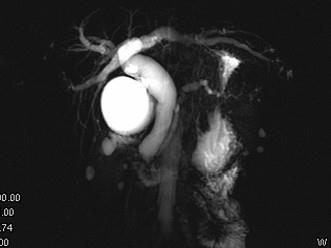

问题 男,48岁,进行性黄疸,发热,腹胀,影像检查如图,最佳的诊断是 ( )

选项 A、十二指肠乳头癌 B、胰头癌 C、胆总管结石 D、胆总管癌 E、胆总管囊肿

答案 A